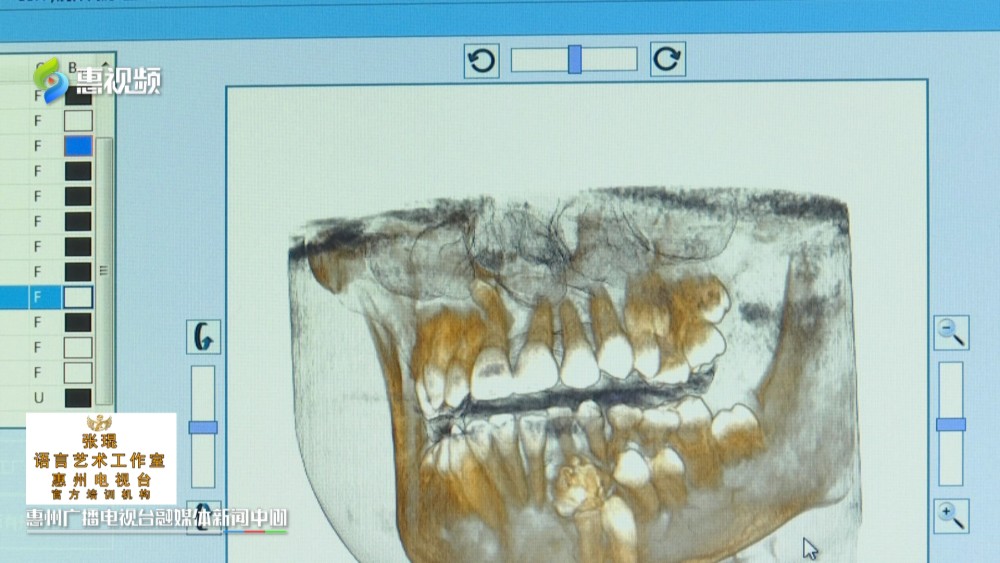

10岁的小婷,一个月前,发现左下颌骨处隆起了一个“大鼓包”,虽然不会疼痛,但肿物影响咀嚼,于是家人带她到医院就医,经诊断,医生确定是一颗“牙瘤”口腔种植,口腔正畸医生。这颗牙瘤就像石榴一样,里面密密麻麻长了25颗畸形牙齿熟悉掌握方丝工矫正技术,

惠州市第三人民医院口腔颌面外科 副主任医师 王俊文:这种算危害比较大,因为她25颗完全就压在那个恒牙的上面,导致恒牙无法长出熟练掌握口腔内科治疗,

最后,医生通过手术帮小婷摘除了肿物,取出25颗畸形牙齿中华人民共和国执业医师法。据介绍,牙瘤并非传统意义上的肿瘤,而是由成牙组织分化、发育形成的错构瘤口腔临床执业医师。与天然牙的发育形成类似,肿物中含有成熟的牙釉质、牙本质、牙骨质和牙髓组织口腔医学技术。在生长发育过程中,当牙瘤完全钙化后,这些结构错乱,或相对有序的牙体组织,会被外周的纤维结缔组织囊包裹,继而影响恒牙发育口腔修复工艺